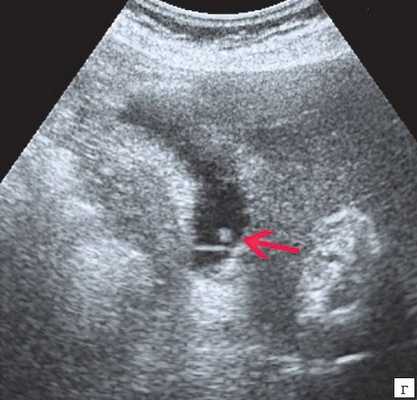

- Ультразвуковая диагностика. К визуализирующим методам диагностики холангита относятся УЗИ брюшной полости и печени, ультрасонография желчных путей. С их помощью удается получить изображение желчных протоков, выявить их расширение, определить наличие структурных и очаговых изменений в печени.

Инструментальная диагностика

В первую очередь пациентам с подозрением на холедохолитиаз проводят ультразвуковое исследование желчевыводящей системы, причём его используют на протяжении всего периода болезни, чтобы отследить динамику лечения. УЗИ помогает оценить состояние протока поджелудочной железы, показывает ворота печени и забрюшинное пространство. Иногда ультразвуковое исследование не позволяет рассмотреть камни в желчном протоке из-за вздутия кишечника, толстой передней брюшной стенки или скопления различных веществ в области ворот печени. Однако в 90 % случаев УЗИ справляется со своей задачей. В некоторых случаях УЗИ также помогает дифференцировать холедохолитиаз и опухоли в печени, желчном пузыре и протоках [7] [8] [9] .

Иногда применяют чрескожную чреспечёночную холангиографию (ЧЧХГ), суть которой заключается в следующем: под контролем УЗИ врач прокалывает желчный проток через кожу и ткань печени, вводит контрастирующее вещество и под рентген-контролем определяет уровень сужения [1] [3] [6] . Метод актуален при сужении нижней части протока или нескольких его частей [20] [21] .